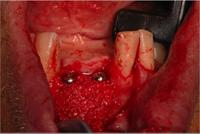

3.

Mesh

removed

4. Implants placed